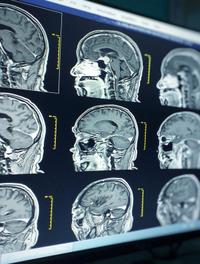

La neuro-imagerie joue un rôle de premier plan dans le diagnostic positif des hémorragies intracérébrales spontanées non traumatiques. [...]